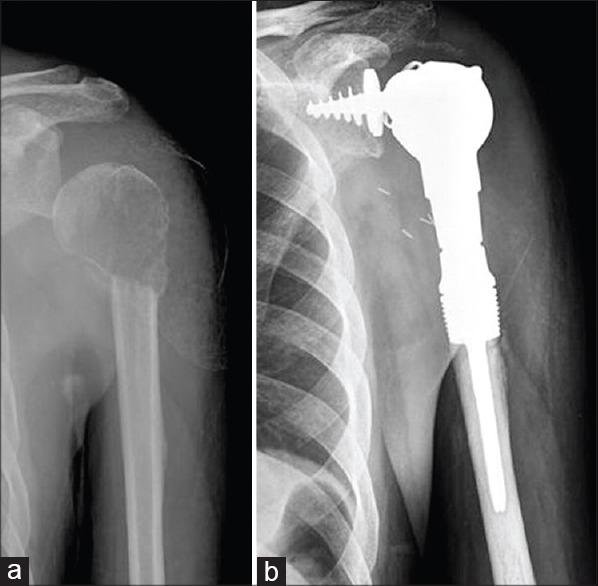

Skeletal metastasis is a common cause of severe morbidity, reduction in quality of life (QOL) and often early mortality. Its prevalence is rising due to a higher rate of diagnosis, better systemic treatment, longer lives with the disease and higher disease burden rate. As people with cancer live longer and with rising sensitivity of body imaging and surveillance, the incidence of pathological fracture, metastatic epidural cord compression is rising and constitutes a challenge for the orthopedic surgeon to maintain their QOL. Metastatic disease is no longer a death sentence condemning patients to "terminal care." In the era of multidisciplinary care and effective systemic targeted and nontargeted therapy, patient expectations of QOL, even during palliative end of care period is high. We lay emphasis on proving the diagnosis of metastasis by biopsy and histopathology and discuss imaging modalities to help estimate fracture risk and map disease extent. This article discusses at length the evidence and decision-making process of various modalities to treat skeletal metastasis. The modalities range from radiation including image-guided, stereotactic and whole body radiation, systemic targeted or hormonal therapy, spinal decompression with or without stabilization, extended curettage with stabilization, resection in select cases with megaprosthetic or biological reconstruction, percutaneous procedures using radio frequency ablation, cementoplasties and discusses the role of emerging modalities like high frequency ultrasound-guided ablation, cryotherapy and whole body radionuclide therapy. The focus lies on the role of multidisciplinary care, which considers complex decisions on patient centric prognosis, comorbidities, cost, feasibility and expectations in order to maximize outcomes on QOL issues.

骨转移是导致严重发病、生活质量(QOL)下降以及常出现早期死亡的常见原因。由于诊断率提高、全身治疗效果更好、患者带病生存时间延长以及疾病负担率上升,其患病率正在上升。随着癌症患者生存期延长以及身体成像和监测的敏感性提高,病理性骨折、转移性硬膜外脊髓压迫的发生率正在上升,这对骨科医生维持患者的生活质量构成了挑战。转移性疾病不再是宣判患者“临终关怀”的死刑判决。在多学科护理以及有效的全身靶向和非靶向治疗时代,即使在姑息性临终关怀阶段,患者对生活质量的期望也很高。我们强调通过活检和组织病理学来证实转移瘤的诊断,并讨论有助于评估骨折风险和描绘疾病范围的成像方式。本文详细讨论了治疗骨转移的各种方式的证据和决策过程。这些方式包括放疗,如影像引导放疗、立体定向放疗和全身放疗、全身靶向或激素治疗、有或无内固定的脊柱减压、扩大刮除术加内固定、在某些病例中进行假体或生物重建的切除术、使用射频消融、骨水泥成形术的经皮手术,并讨论了高频超声引导消融、冷冻疗法和全身放射性核素治疗等新兴方式的作用。重点在于多学科护理的作用,它考虑以患者为中心的预后、合并症、成本、可行性和期望等复杂决策,以最大限度地提高生活质量相关问题的治疗效果。